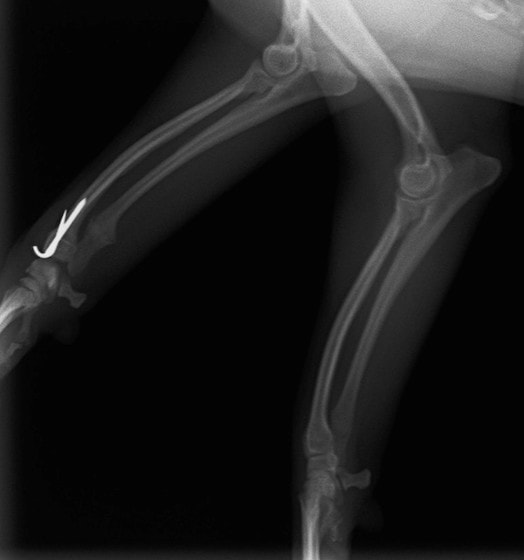

症例3:キルシュナーワイヤーのピンニングによる整復

ペルシャ猫 11ヶ月齢 雄

他院にて左大腿骨遠位の成長板骨折(salter-harrisⅠ型)が認められており、治療相談を目的として来院。当院にて、キルシュナーワイヤーを用いたピンニングにより骨折部位の整復を行いました。術後の経過は良好で、現在も経過観察中です。

術前レントゲン